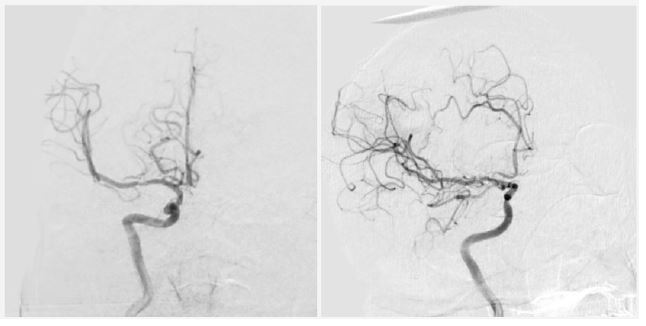

Twenty-four hours post-admission, his neurological status worsened (GCS decreased by 4 points), and a CT scan showed a significant midline shift. A right-sided frontotemporoparietal decompressive craniectomy was performed. Postoperatively, his GCS improved to 14 and motor strength improved to 3/5 on the Lovett scale (Figure 2). A Computed Tomography Angiography (CTA) performed 48 hours after surgery showed restored flow in the M1 and distal branches of the right MCA (Figure 3). A confirmatory cerebral angiogram at two weeks demonstrated patent flow throughout the MCA distribution (Figure 4).

Figure 2: Post-decompressive craniectomy computed tomography. Evidence of persistent ischemia is observed in the right MCA territory.

Figure 3: Computed tomography angiography 48 hours after decompressive craniectomy, showing vascular flow in the right MCA territory.